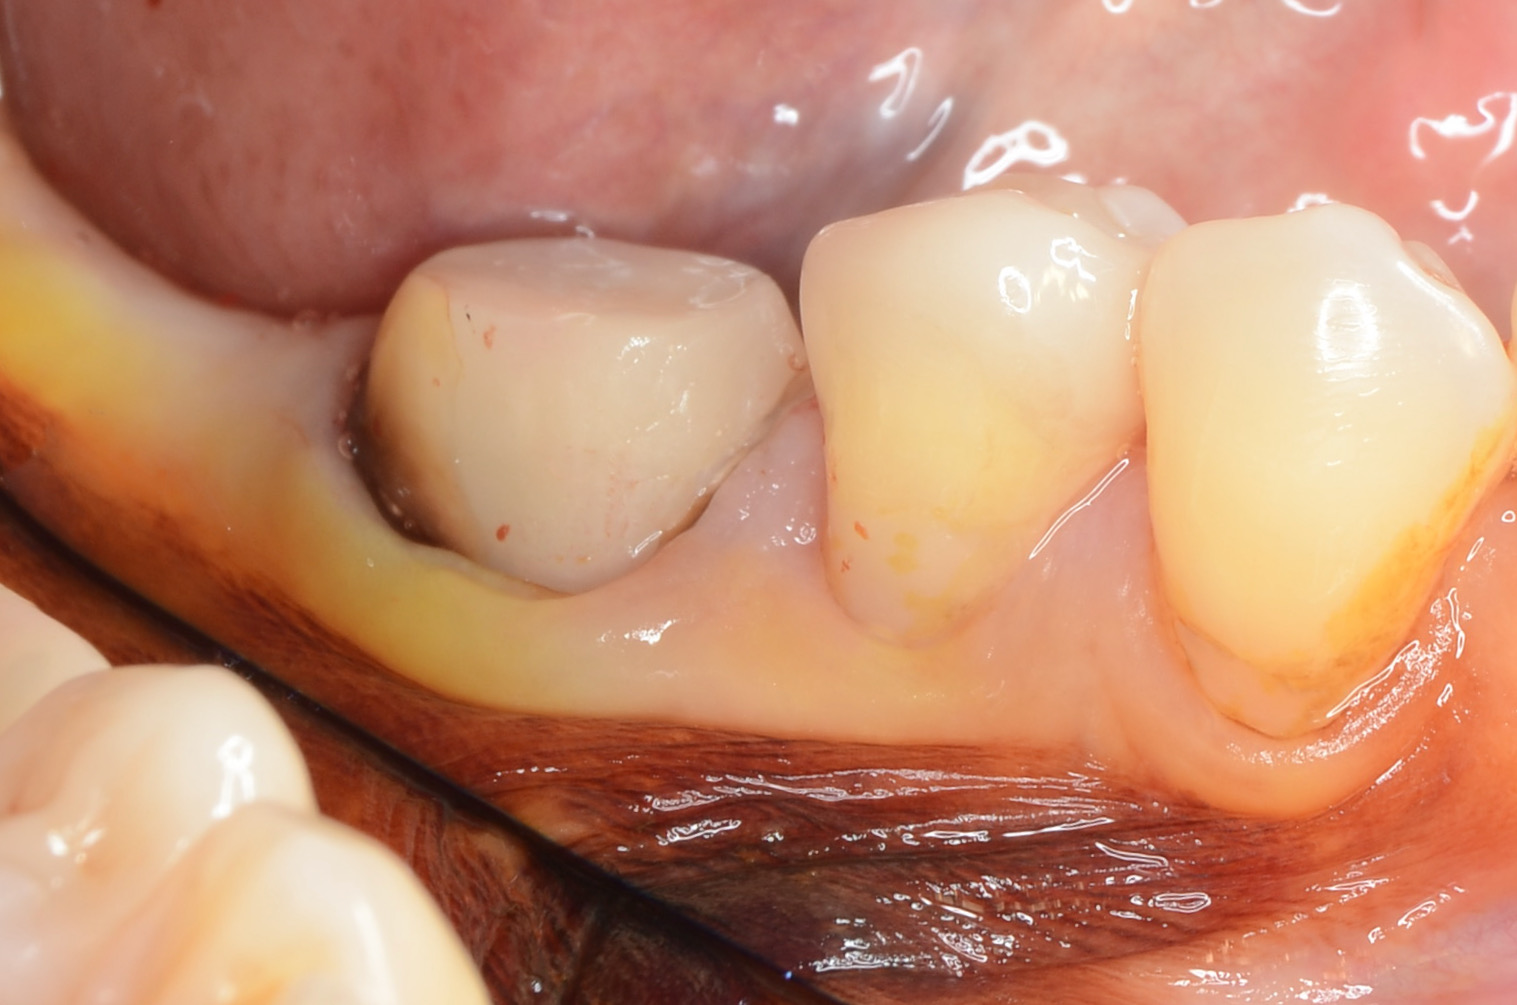

術前

ヨードで染めると角化歯肉幅は十分あります。 -